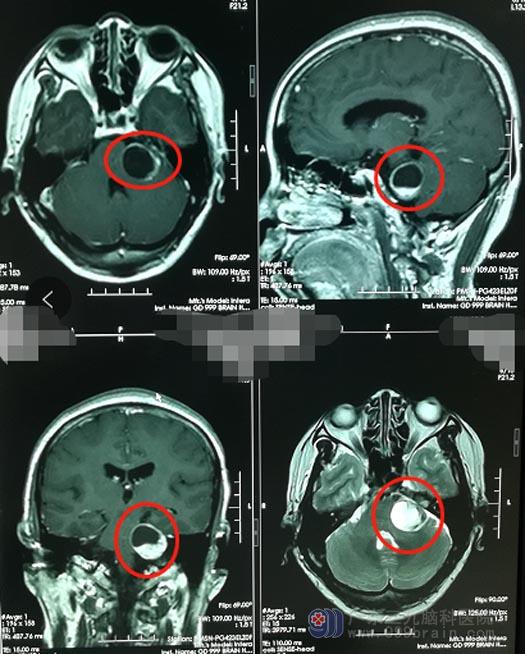

CT、MR等影像检查均提示肿瘤位于左侧桥小脑角区,结合陈大姐的之前症状,神经外五科治疗团队判断陈大姐患听神经瘤的可能性大,且符合手术指征,应尽快进行手术治疗。